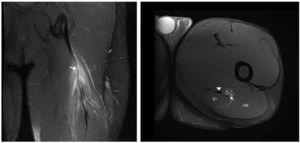

Eighteen years old professional football player suffered the same kind of pain in the same kind of circumstances. Clinical signs were exactly similar than the previous acute hamstring strain described but the MRI exam showed different images (Figs. 3 and 4) because the injury was located in the free tendon of BF. The length of free-tendon was 8.5 cm and the injury was located at 6.5 cm from the ischial tuberosity. Due to the long time of recovery and a high reinjury rate, surgical treatment should be considered. Excision of the scar tissue, including the torn portion of the tendon was then performed and tension-free suturing of the belly remnant of the biceps femoris to the adjacent semitendinosus. In order to provide tension to the tendon and reinforcement with anchors in ischial tuberosity (Figs. 3 and 4).

Figure 4 Coronal T2 Fat-saturated image of left hamstring in post surgery follow-up, that show the metallic anchor in ischial tuberosity (arrowhead) and peritendinous sutures represented by magnetic susceptibility peritendinous artifacts (arrow).